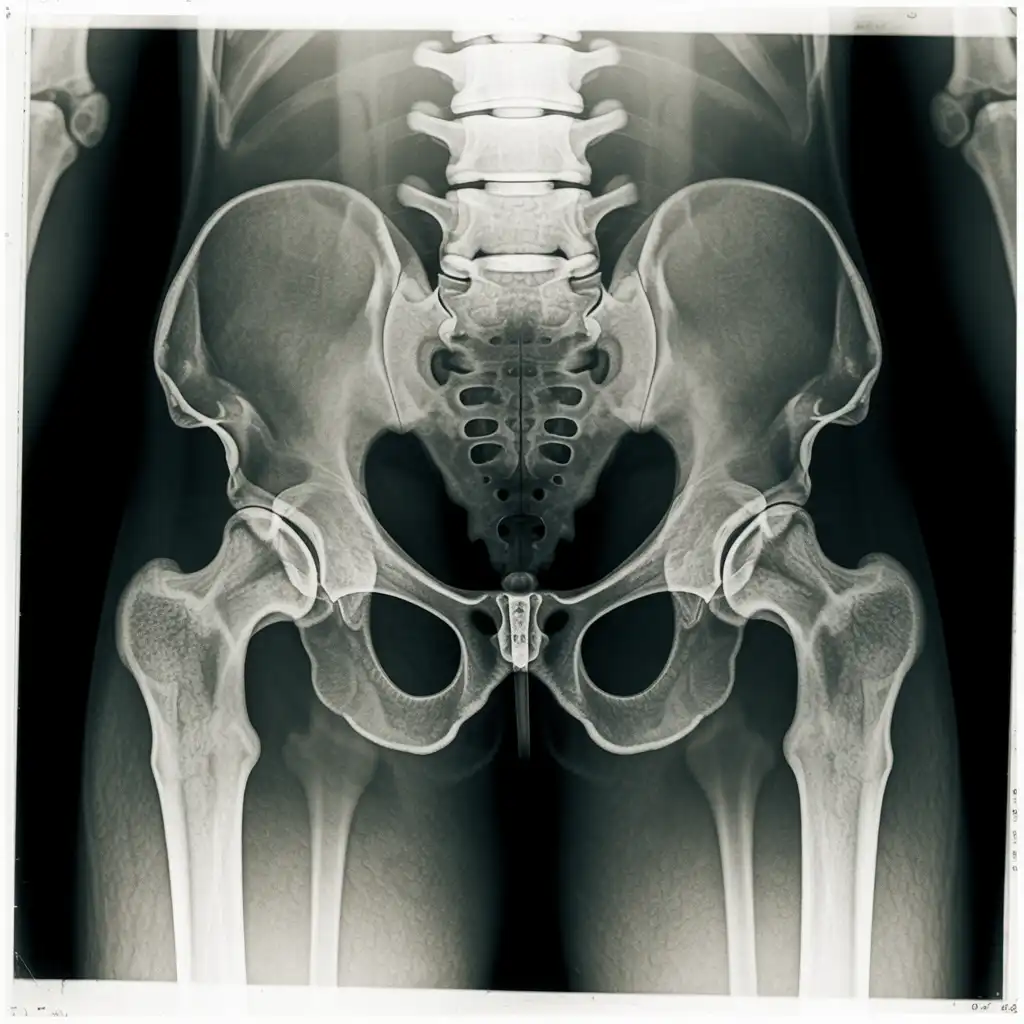

Una radiografia a domicilio è un esame radiologico eseguito da un tecnico specializzato che viene a casa tua con apparecchiature digitali portatili. L’esame si svolge sul posto, senza spostare il paziente e con la stessa qualità di una struttura ospedaliera.

Dopo l’acquisizione delle immagini, queste vengono inviate al medico radiologo che referta rapidamente e ti invia tutto in formato digitale. Un servizio comodo, sicuro e ideale per chi ha difficoltà negli spostamenti.